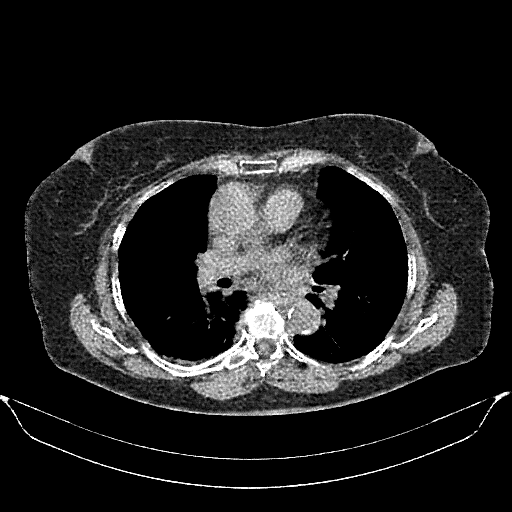

Generated VENOUS CT scan (A→B translation)

Full window (WL 1023.5, WW 4095 β†’ Low βˆ’1024, High +3071)

Actual HU range: [-1024.0, 1390.1]